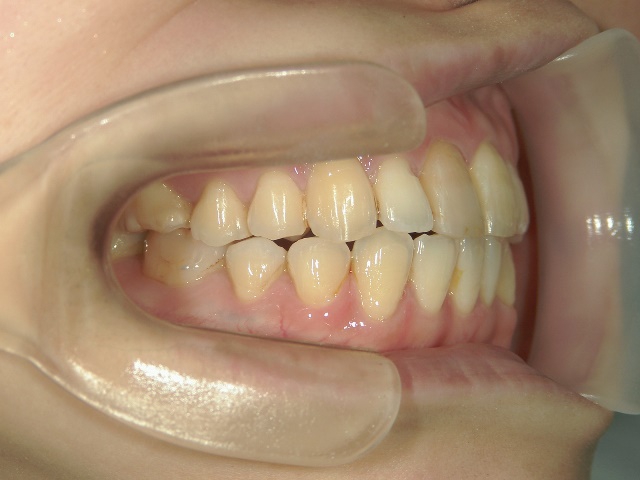

矯正歯科 治療前矯正歯科 治療前

no.37_7548_治療前_右.JPGno.37_7548_治療前_正面.JPGno.37_7548_治療前_左.JPG